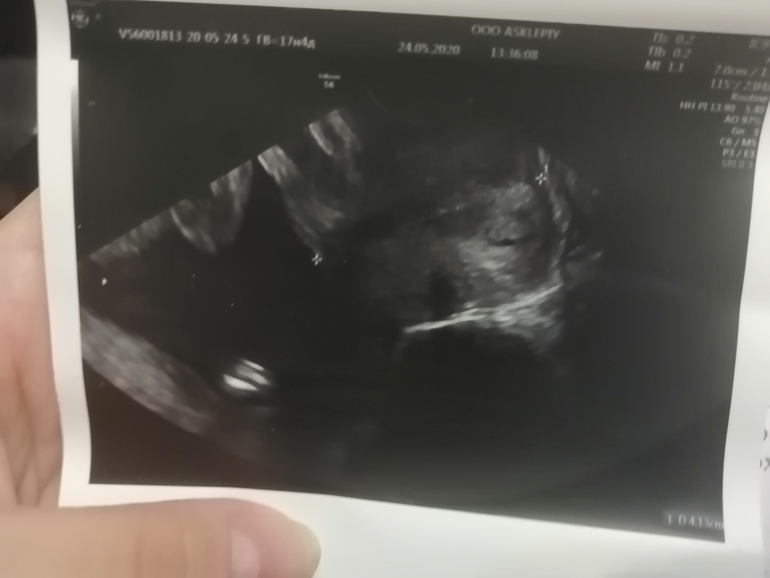

На этой фотке я вообще не понимаю что... И зачем вообще он мне её сделал... Может кто понимает.. Помогите!!! Я, конечно, сомневаюсь, что здесь можно что то понять.. Но может я просто не понимаю...

Это фото цервикального канала, вашей шейки матки от внутреннего зева до внешнего.

По мне, так это малыш попой кверху. Между плюсиками- бедренную кость измеряли (от копчика до коленки)

Ага, большая попа, в правом углу, от неё влево две ножки, согнутые в коленях. А внизу справа белая самая светлая - это плечевая кость ручки.

А слева по срезу фотки - так это петля пуповины

А в самом верхнем левом углу - это дальняя ножка, голень...

Нет, на этой фотке пол не видно, он с другой стороны тела.😊